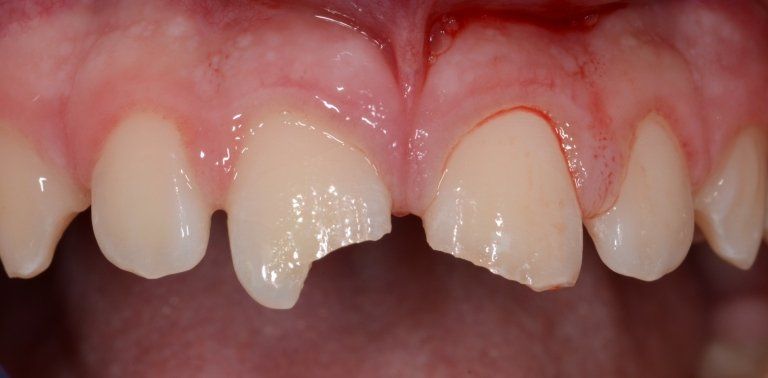

La frattura degli incisivi permanenti in un giovane paziente. I denti verranno ricostruiti in maniera diretta, alla poltrona.

Il caso può essere visionato in maniera più estesa nella sezione "traumi dentari" delle Prestazioni Bambini.